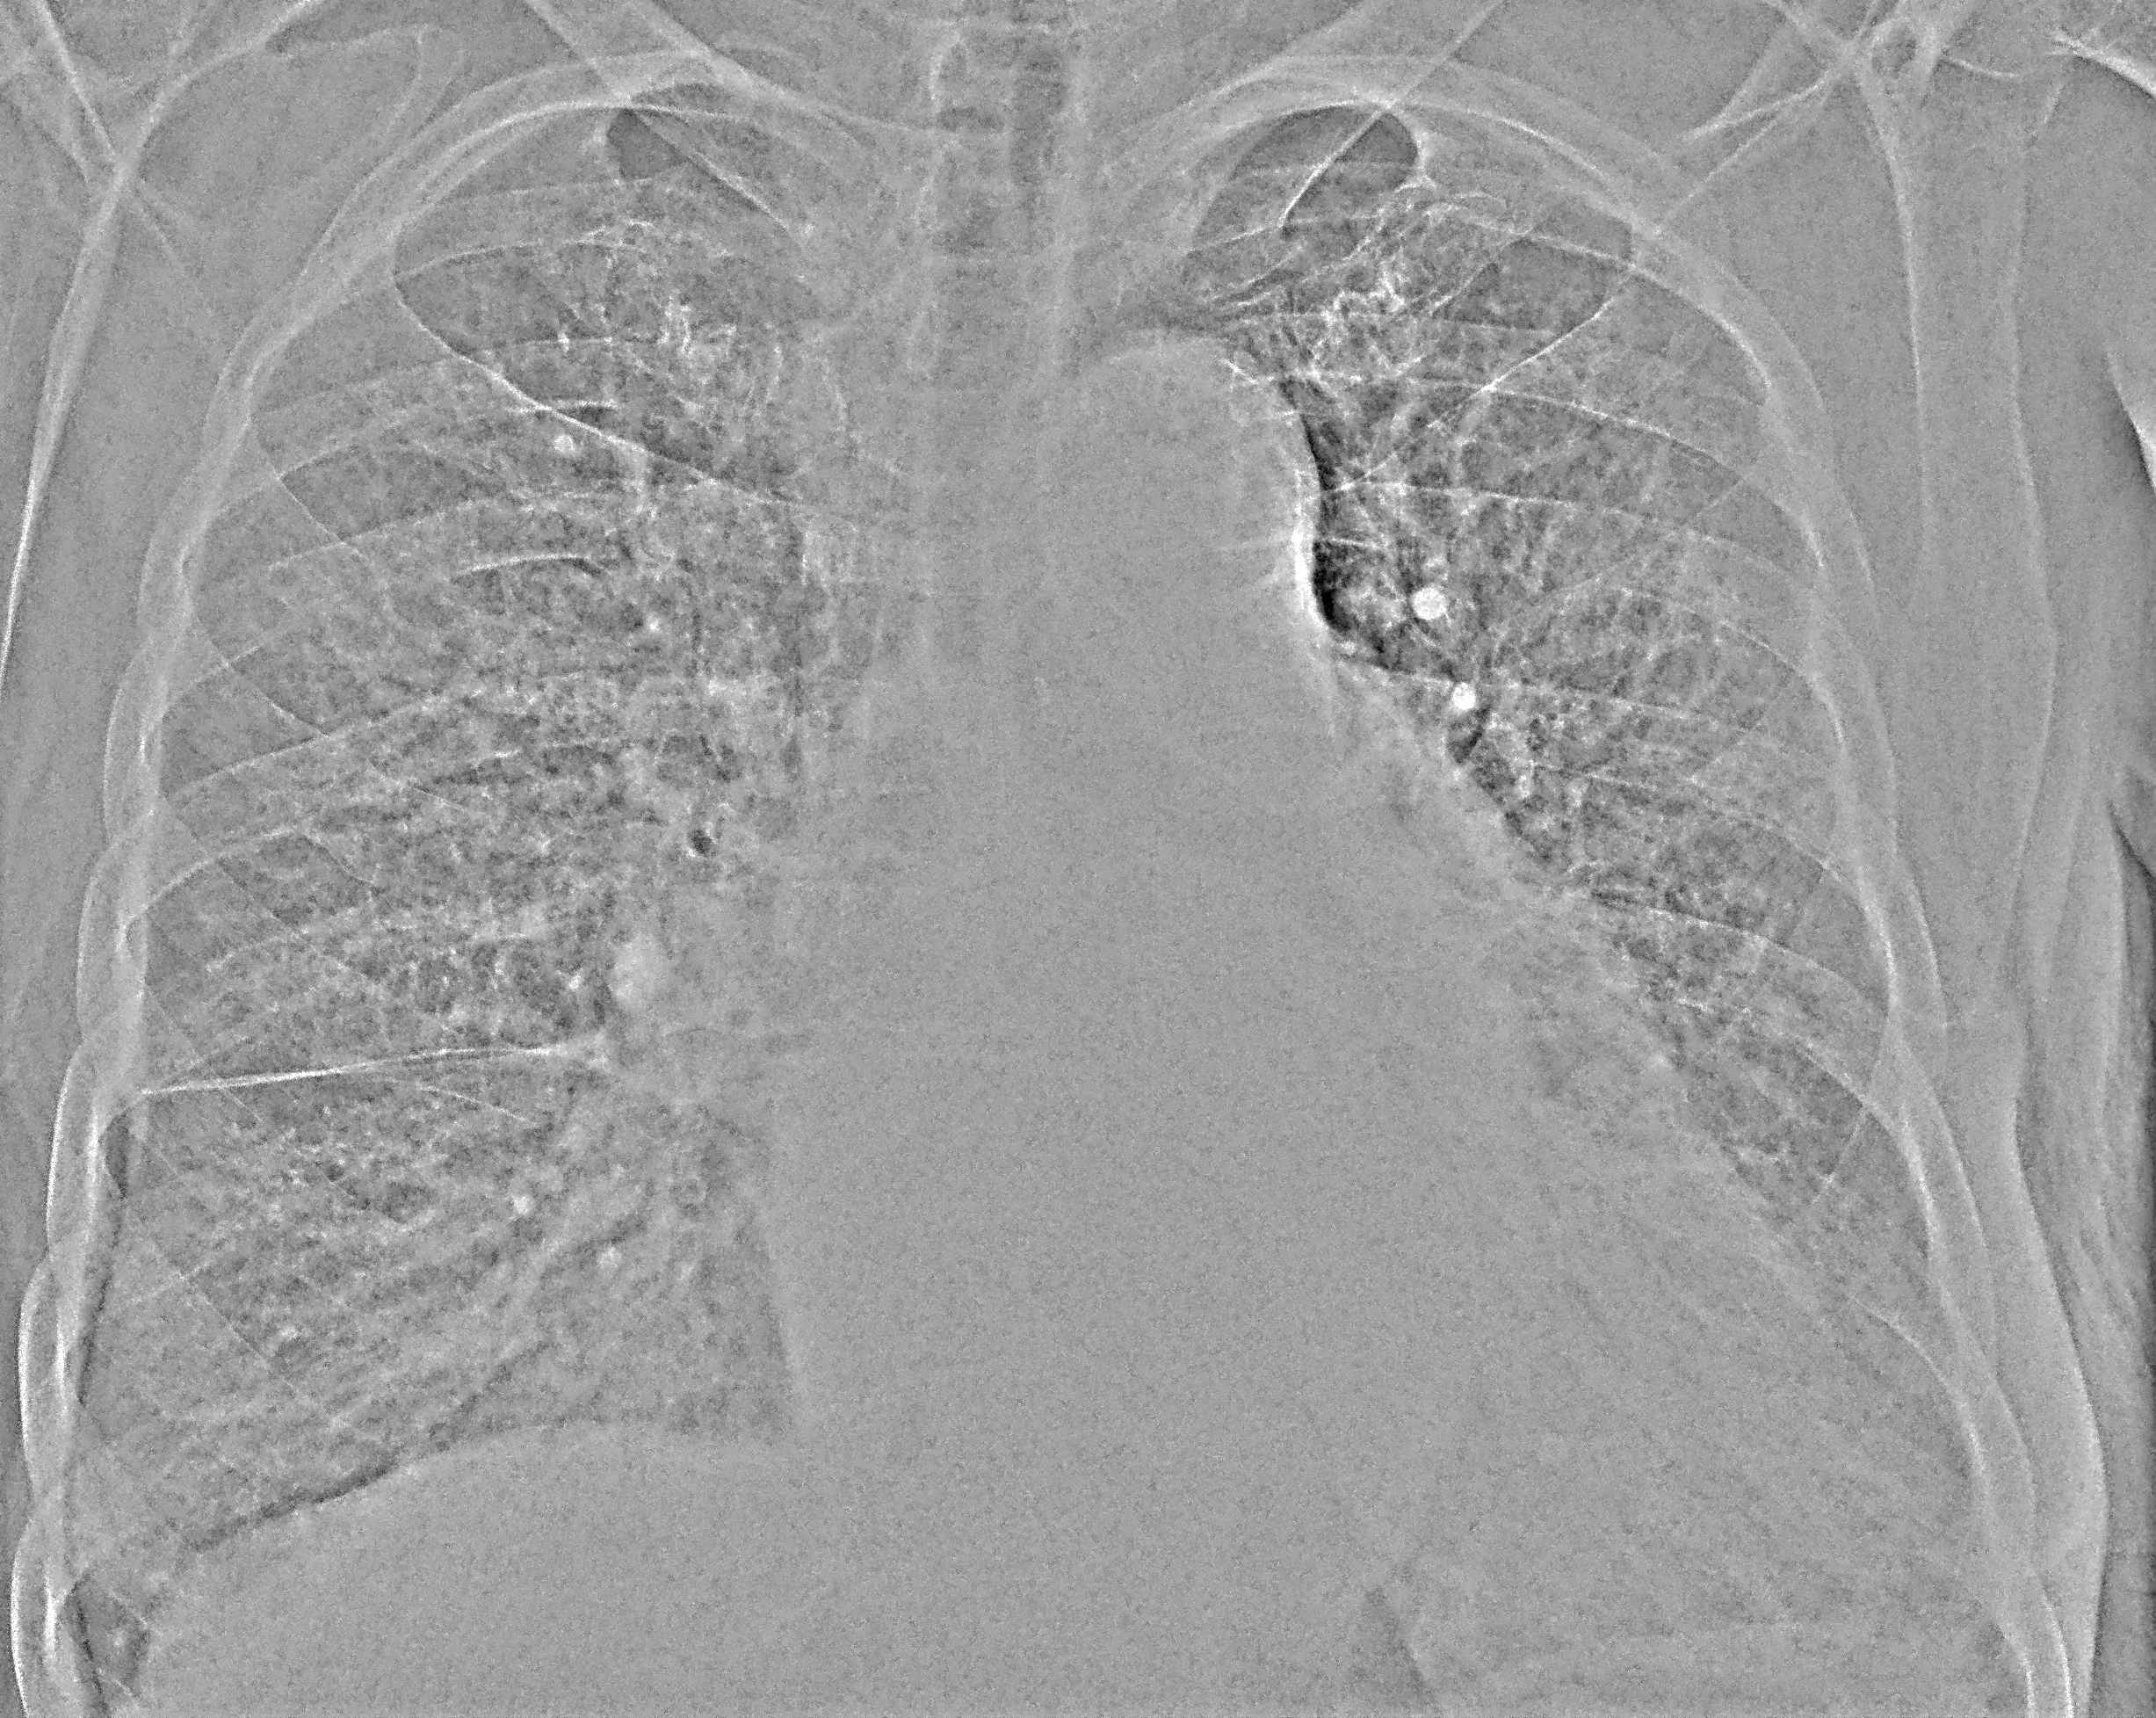

Двусторонняя пневмония